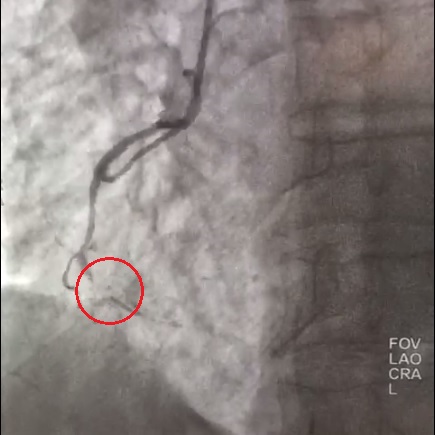

Сотрудники отделения рентгенохирургии в соответствии с самыми современными рекомендациями выполнили стентирование пораженных участков артерий и полностью устранили все сужения, имплантировав 3 стента с лекарственным покрытием.

Результаты стентирования